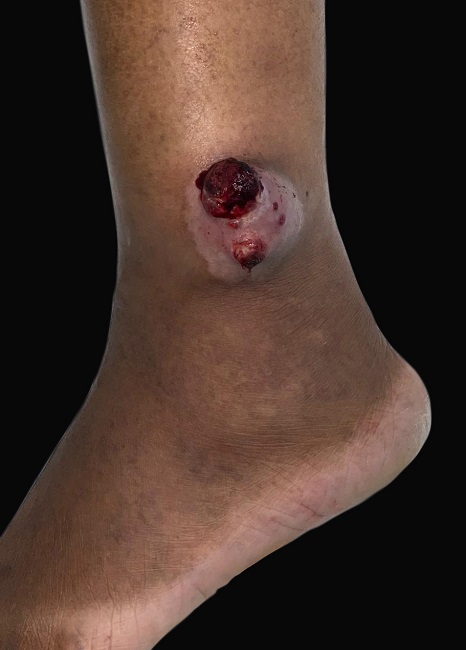

Mulher, 49 anos, negra, dona de casa, apresentava tumoração friável, com superfície sangrante, consistência fibrosa, aderida, de contorno definido, localizada no maléolo lateral direito, medindo 7,0x5,5cm, de crescimento progressivo nos últimos nove meses (Figuras 1 and 3). Referia episódios de sangramento associados à dor local. Procurou assistência médica, sendo tratada como infecção bacteriana, com antibioticoterapia, sem melhora.

Apresentava como antecedentes: trombose de veia porta, insuficiência cardíaca e hipertensão arterial. Não foram identificados linfadenopatias, visceromegalias ou linfedema. Os diagnósticos aventados foram melanoma amelanótico, sarcoma e carcinoma de Merkel.